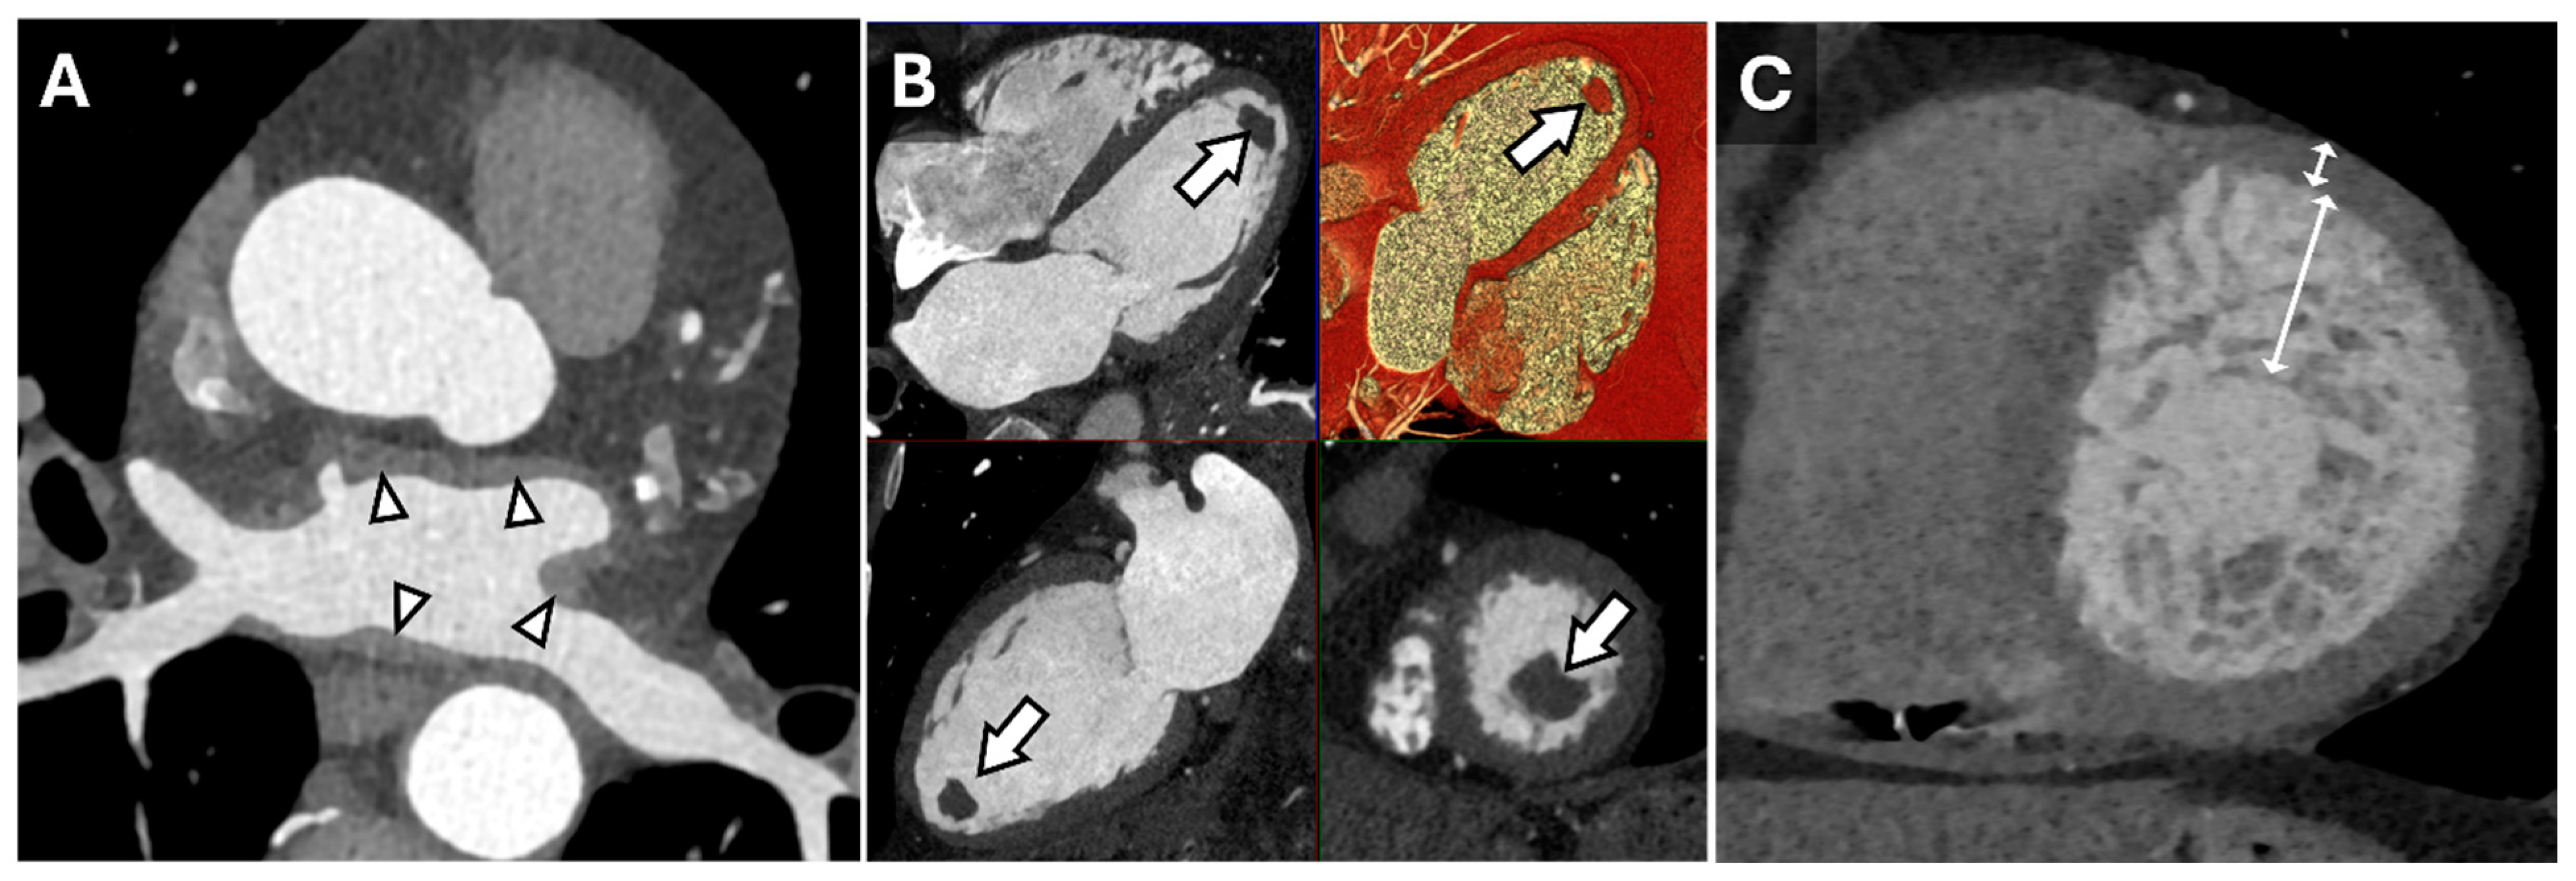

Cardiac CT is well-suited for the evaluation of morphologic features, such as wall thickness and chamber dimensions, given its excellent spatial resolution and volumetric acquisition. It is worth noting that most CT coronary angiography is performed during end-systole or mid-diastole, which may result in an overestimation of wall thickness and underestimate end-diastolic volumes [14]. Additional features, such as atrial wall thickening, left ventricular thrombus, or non-compaction, can be identified regardless of the cardiac cycle phase (Figure 1) [15]. Thrombus detection, in particular, is often more reliable with CT than echocardiography, as it appears as a filling defect in a contrast-filled chamber. Beyond cardiac morphology, CT can reveal extracardiac findings that may provide broader diagnostic insights. For instance, bilateral hilar adenopathy, visible on cardiac CT, may suggest sarcoidosis, expanding the diagnostic perspective beyond cardiac pathology (Figure 2).

Figure 1.

Cardiac Findings and CT Imaging. Axial reconstruction from a contrast-enhanced cardiac CT (A) demonstrating irregular left atrial wall thickening (arrowheads) reflecting amyloid deposition in the setting of cardiac amyloidosis. Multiplanar (HLA, VLA, SAX, 3D) diastolic images (B) from a contrast-enhanced cardiac CT in a patient with a left ventricular apical thrombus (arrows). Short-axis end-diastolic image from a contrast-enhanced cardiac CT in a patient with myocardial non-compaction (C) demonstrating very prominent trabeculation of the mid-apical left ventricle with an increased ratio of non-compacted to compacted myocardium measuring >> 2.3:1 (double-headed arrows).